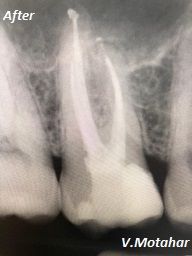

Root Canal treatment on Lower molar tooth immediate after the Root Filling!

before

after

Root canal treatment on three rooted tooth! which had 4 canals!